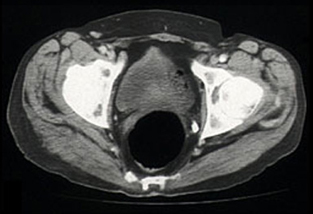

When the diagnosis was established, methotrexate was also stopped. The patient presented for CHOP-based chemotherapy (cyclophosphamide, adriamycin, vincristine, prednisolone) 19 days later (2 months after he stopped taking cyclosporin). The palpable swelling of the right buttock had disappeared, and a repeat CT scan confirmed resolution of the previously diffuse muscle swelling (Box, Figure 4). Chemotherapy was withheld.